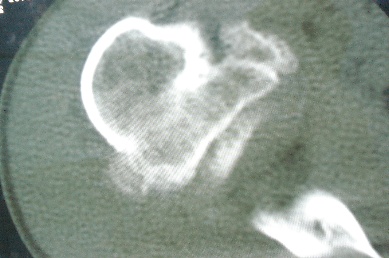

右上肢活动不便多年,最近加重。右肱骨肿瘤,请会诊!

骨软骨瘤恶变可能性大

右肱骨近断骨软骨瘤伴临近关节退变.有无恶变建议进一步检查.

右肱骨近断骨软骨瘤伴临近关节退变。

病变边缘轮廓清晰无骨质破坏,邻近软组织不肿胀,不支持肿瘤恶变。